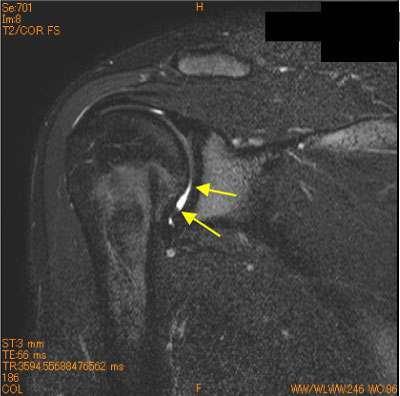

10代女性、ソフトボール歴11年、投球時痛、 関節窩前下方の軟骨欠損を認めている。

腱板損傷、関節唇損傷が疑われていたがintactであった。

先入観にとらわれない読影が重要である。